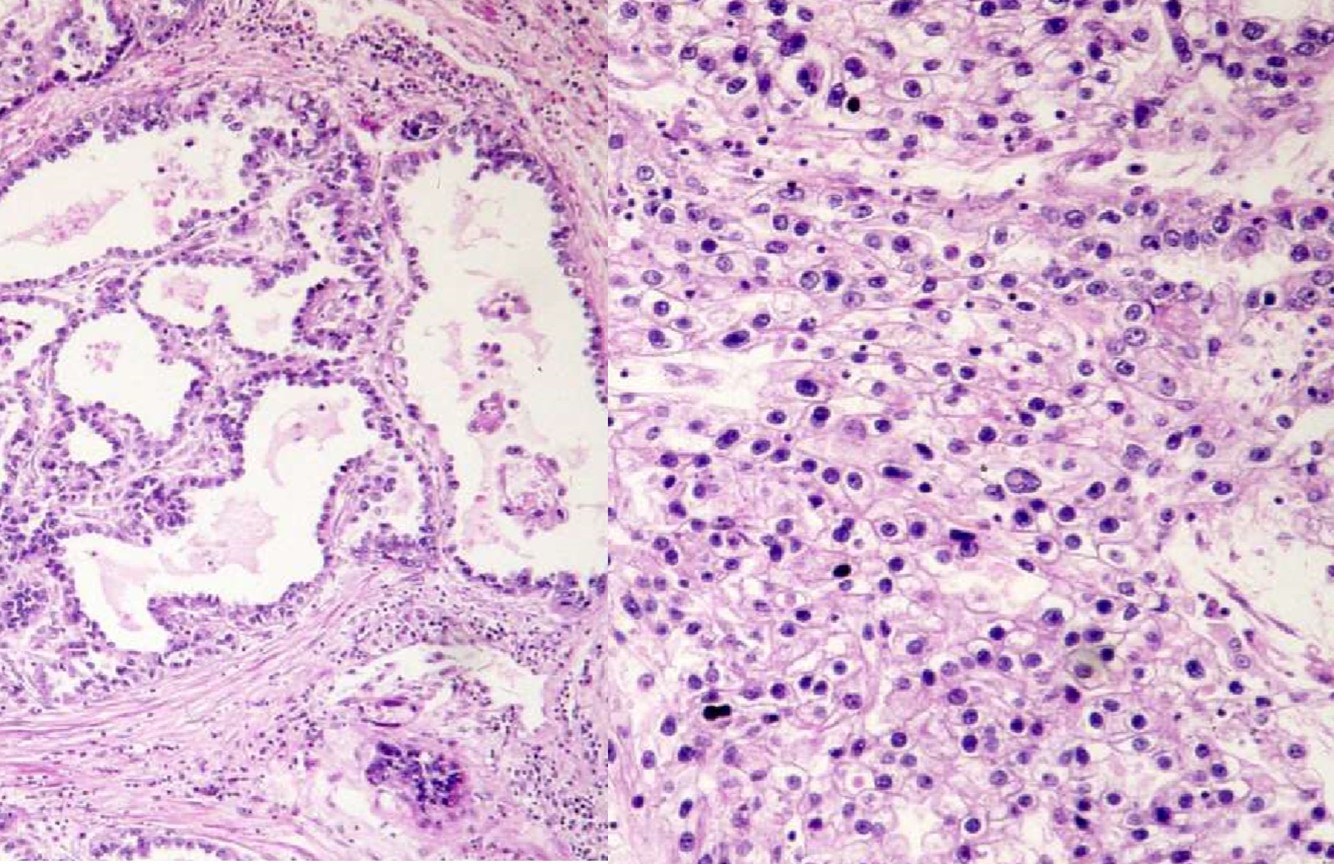

COLLECTING DUCT CARCINOMA

- AKA Bellini duct carcinoma

- Firm mass in medulla

- Infiltrating tubular or tubulopapillary

- Desmoplastic stroma

- +/- cytoplasmic and intraluminal mucin

- High grade

- Poor prognosis

- Rule out met

- (+) E-cadherin, PAX8, L&Hmw CK (var)

- (-) AMACR, racemase, CD10, CK20